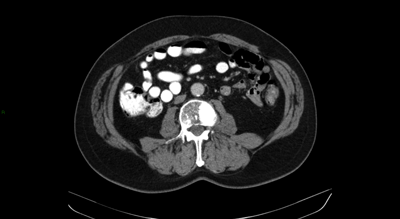

A 66-year-old man presented with a locally advanced T3b N1 prostate cancer in 2011, with an initial PSA of 33. He was treated with robotic prostatectomy and lymph node dissection followed by adjuvant prostate bed radiotherapy. Although immediate post treatment PSA levels were undetectable he had a PSA relapse in September 2012 to 2.1. Whole body MRI and Choline PET showed an apparent isolated left iliac lymph node recurrence (Figure 4). He went on to receive stereotactic radiotherapy (33Gy in 3 fractions to the lymph node - Figure 5). Follow-up imaging has shown a complete radiological response within the treated node. Eighteen months after treatment his PSA has started to rise again and most recent imaging has shown the development of a lymph node on the opposite side of the pelvis with no other sites of disease. He subsequently had further stereotactic radiotherapy to the right pelvic side wall nodes in July 2014. His PSA has dropped to 0.02 on his most recent check in January 2015.

Figure 4: Isolated pelvic lymph node recurrence on whole body MRI and Choline Pet and response to treatment.